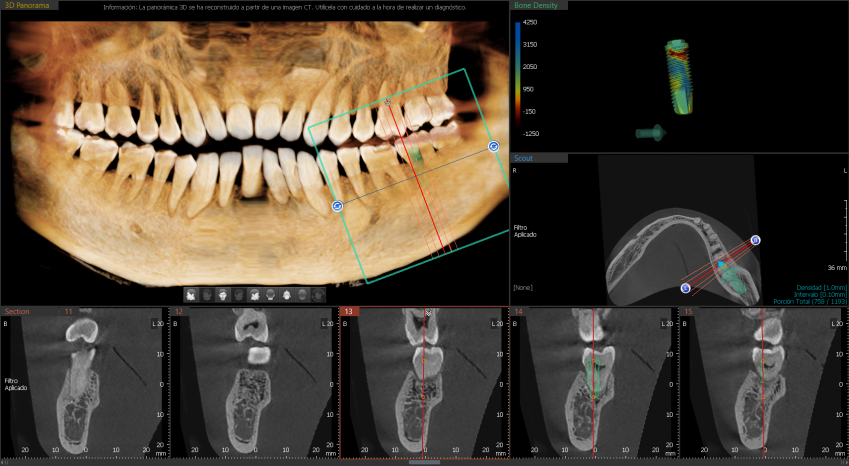

FOV INTEGRAL PARA IMAGEN 3D

Las imágenes 3D permiten realizar diagnósticos precisos para planificar los tratamientos dentales. Incluye la áreas maxilar y mandibular en una sola exposición. Ideal para cirugías de implantes y diagnósticos en cirugía oral.